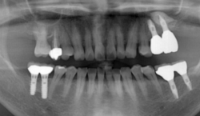

インプラントは、あごの骨に人工の歯の根(フィクスチャー・チタン製など)を埋め込み、その上に人工の歯を固定する、歯科の最先端医療技術です。当院では、最新のCT機械を導入し、以前にも増して、より精度の高い診断が可能となります。

インプラントを埋入し、縫合後に次の段階へと移ります。